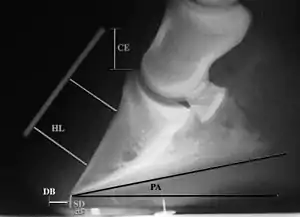

Radiographs

Radiographs are an important part of evaluating the laminitic horse. They not only allow the practitioner to determine the severity of the episode, which does not always correlate with degree of pain,[1] but also to gauge improvement and response to treatment. Several measurements are made to predict severity. Additionally, radiographs also allow the visualization and evaluation of the hoof capsule, and can help detect the presence of a lamellar wedge or seromas.[1] The lateral view provides the majority of the information regarding degree of rotation, sole depth, dorsal hoof wall thickness, and vertical deviation.[1][17] A 65-degree dorsopalmar view is useful in the case of chronic laminitis to evaluate the rim of the coffin bone for pathology.[1]

- Radiographic measurements

Several radiographic measurements, made on the lateral view, allow for objective evaluation of the episode.

- Coronary extensor distance (CE): the vertical distance from the level of the proximal coronary band to the extensor process of P3. It is often used to compare progression of the disease over time, rather than as a stand-alone value. A rapidly increasing CE value can indicate distal displacement (sinking) of the coffin bone, while a more gradual increase in CE can occur with foot collapse. Normal values range from 0–30 mm, with most horses >12–15 mm.[1]

- Sole depth (SD): the distance from the tip of P3 to the ground.

- Digital breakover (DB): distance from the tip of P3 to the breakover of the hoof (dorsal toe).[1]

- Palmar angle (PA): the angle between a line perpendicular to the ground, and a line at the angle of the palmar surface of P3.

- Horn:lamellar distance (HL): the measurement from the most superficial aspect of the dorsal hoof wall to the face of P3. 2 distances are compared: a proximal measurement made just distal to the extensor process of P3, and a distal measurement made toward the tip of P3. These two values should be similar. In cases of rotation, the distal measurement will be higher than the proximal. In cases of distal displacement, both values will increase, but may remain equal. Therefore, it is ideal to have baseline radiographs for horses, especially for those at high-risk for laminitis, to compare to should laminitis ever be suspected. Normal HL values vary by breed and age:[1]